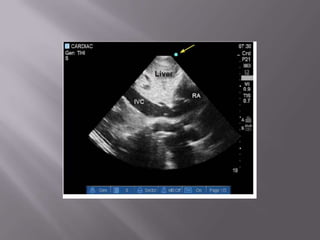

Ferramenta não apenas diagnóstica como de monitorização  Fundamental na abordagem do choque e da dispnéia  Permite em segundos descartar embolia pulmonar e tamponamento cardíaco como causas do choque  Usado na PCR – determinar causa reverível – durante a checagem do Pulso!  Transtorácico ou Transesofágico?